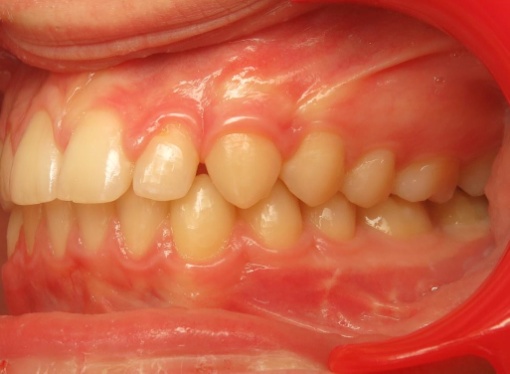

1 - Arcades dentaires avant-après

Les arcades dentaires montrent un décalage majeur de classe II, avec des incisives inférieures en position très reculée, venant directement au contact du palais. Cette configuration traduisait un déséquilibre squelettique important entre maxillaire et mandibule. Le traitement a consisté en une préparation orthodontique rigoureuse, suivie d’une chirurgie orthognathique permettant de repositionner les bases osseuses et de restaurer une occlusion fonctionnelle.